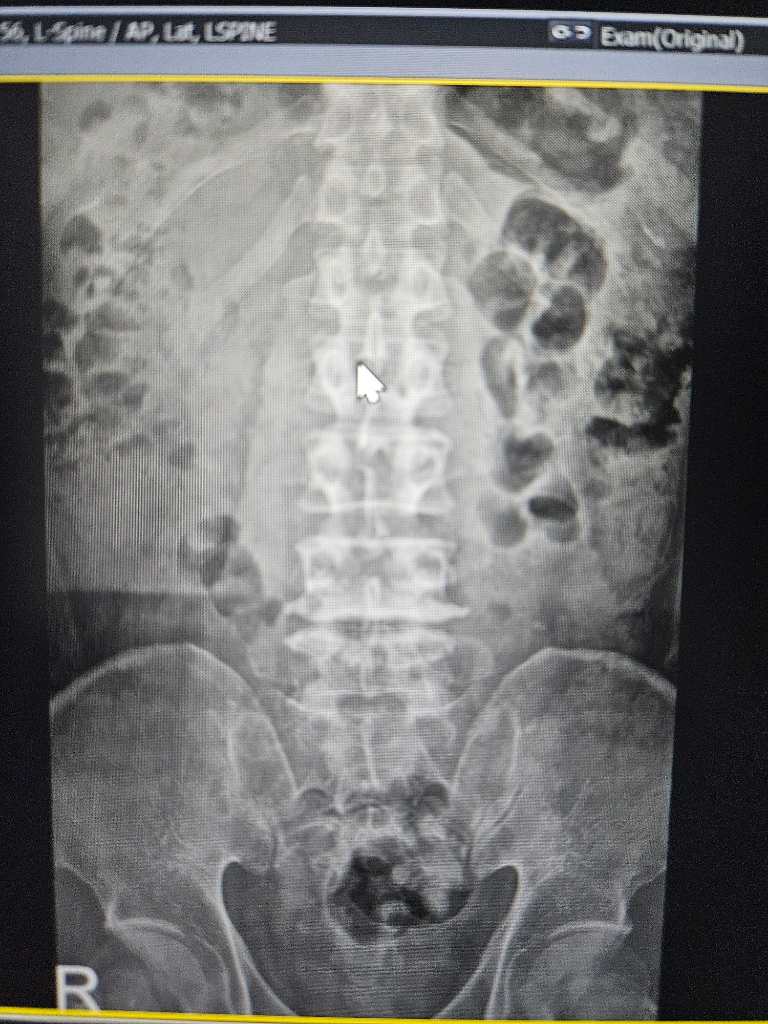

수술해야될 정돈지 사진보시고 확인좀 해주세요

척추분리증과 전방전위증등으로 통증이 너무심한데

허리부터 다리까지 통증이 있고 종아리까지 전기가 찌릿한 증상 누워있을때는 그나마 참을만 한데 그외 다른자세를 하면 통증이 심해집니다

걷는것도 10분이상하면 허리 부터 허벅지 까지 통증이 심하게 생깁니다

척추분리증은 30년 정도 되었고 다른건 10년이 넘은거 같습니다

사진과함께 증상을 종합해봤을때 수술이 필요한지 아니면 보존치료가 더 나은지 궁금 합니다

보내주신 사진만으로는 정확한 진단을 내리기 어렵습니다. 정확한 진단을 위해서는 전문의의 진찰과 검사가 필요합니다. 하지만 사진과 증상을 종합해보면 수술을 고려해볼 수 있는 수준으로 보입니다.

척추분리증과 전방전위증은 척추뼈가 정상적인 위치에서 벗어나 발생하는 질환입니다. 이 질환은 허리와 다리에 통증, 저림, 감각 이상 등의 증상을 유발할 수 있습니다.

수술 방법은 여러 가지가 있으며, 환자의 상태에 따라 적절한 방법을 선택합니다. 일반적으로 척추뼈를 고정하는 척추유합술이 시행됩니다.